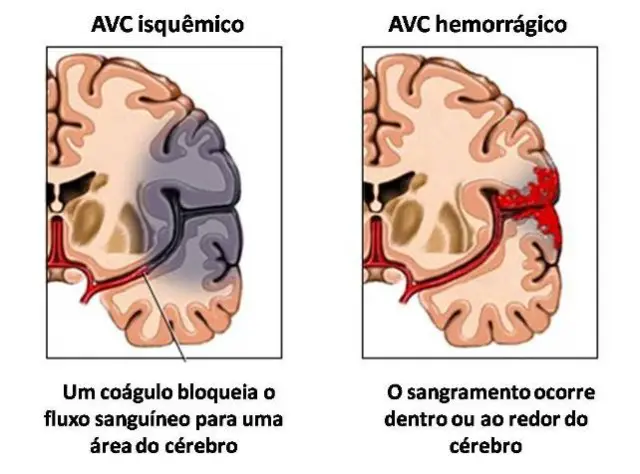

Ela é comum em casos de acidentes vascular cerebral, ou quando há outros danos ao sistema neurológico que fazem com que a pessoa que sofre de tal problema não consiga mais reconhecer a escrita, ou então executar a fala como podia antes de tais acidentes.